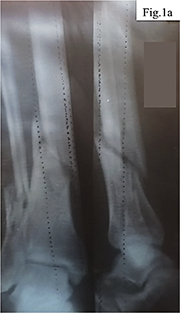

Clinical case. The patient, a 40-year-old man, sustained an injury to the right tibia as a result of tripping over a tree stump while carrying firewood. His medical history included a cervical spine injury after diving into shallow water, which may indicate increased vulnerability to traumatic loads. Initial examination and radiography revealed a closed comminuted fracture of the tibia with intramedullary fragments (Fig. 1).

Considering the nature of the fracture and the need for stable fixation of the fragments, a decision was made to perform open osteosynthesis using metal plates, as shown in Figure 2. The surgical treatment was delayed for two weeks due to implant supply interruptions associated with the military conflict in Ukraine. During the operation, two metal plates with a total of 16 screws were implanted, the wound was closed in layers, and four drains were placed to control postoperative fluid outflow.

The patient’s medical history was systematically reviewed prior to inclusion. Age: 40 years, male sex. No chronic systemic diseases were identified (diabetes mellitus, osteoporosis, autoimmune pathology, or malignancies). No disorders of bone metabolism, immunodeficiency states, or conditions capable of independently impairing osteogenesis were present. The patient had no prior allergic reactions to metals, no episodes of contact dermatitis, no confirmed allergic diseases, and no family history of metal hypersensitivity. No prior orthopedic surgical interventions had been performed. A history of cervical spine injury following a diving accident in youth was noted, indicating a predisposition to traumatic events; no functional neurological deficit was present at the time of the index injury. The patient was a non-smoker and did not consume alcohol regularly. No medications with potential osteosuppressive effects – including corticosteroids, bisphosphonates, or NSAIDs as chronic therapy – were taken prior to the injury. No prior metal implants or metallic dental prostheses had been inserted. The mechanism of the current injury was a low-energy domestic trauma (tripping while carrying firewood), with immediate-onset pain and inability to bear weight, prompting emergency radiographic evaluation. Surgical treatment was performed after a two-week delay due to implant supply interruptions associated with the military conflict in Ukraine. Osteosynthesis was performed using two locking compression plates (LCP) fabricated from 316L stainless steel (Synthes/DePuy, identical manufacturer and material batch for both plates) with 16 cortical and locking screws of the same alloy composition. The use of identical-batch implants excluded mixed-metal galvanic corrosion as an independent confounding variable, although intra-alloy ion release from 316L steel (Ni²⁺, Cr³⁺, Mo²⁺) remained a relevant pathophysiological factor. The choice of stainless steel implants was dictated by the unavailability of titanium alloy constructs under wartime logistics constraints. The osteosynthesis was technically correct, as confirmed by subsequent radiological evaluation. The wound was closed in layers and four drains were placed to control postoperative fluid outflow. Postoperative immobilization protocol: Following osteosynthesis, the operated limb was immobilized using a posterior plaster splint from the level of the metatarsophalangeal joints to the proximal third of the tibia for the first two weeks, in accordance with standard post-osteosynthesis protocols. After suture removal and wound assessment at days 14-16, gradual transition to a removable orthotic walking boot was planned; however, due to logistical constraints during the wartime period, consistent use of orthotic support was suboptimal. Partial weight-bearing with axillary crutches was advised commencing at week 4. Full weight-bearing was deferred until radiographic evidence of early callus formation, assessed at the 8-week follow-up. Analgesic management in the postoperative period consisted of short-term oral NSAID therapy: ibuprofen 400 mg three times daily for the first seven postoperative days, subsequently discontinued. No selective COX-2 inhibitors, systemic corticosteroids, or disease-modifying anti-rheumatic drugs were administered at any point during the observation period. NSAIDs were used transiently and were not considered a confounding factor in the assessment of aseptic inflammation, given their cessation well before the onset of persistent inflammatory symptomatology.